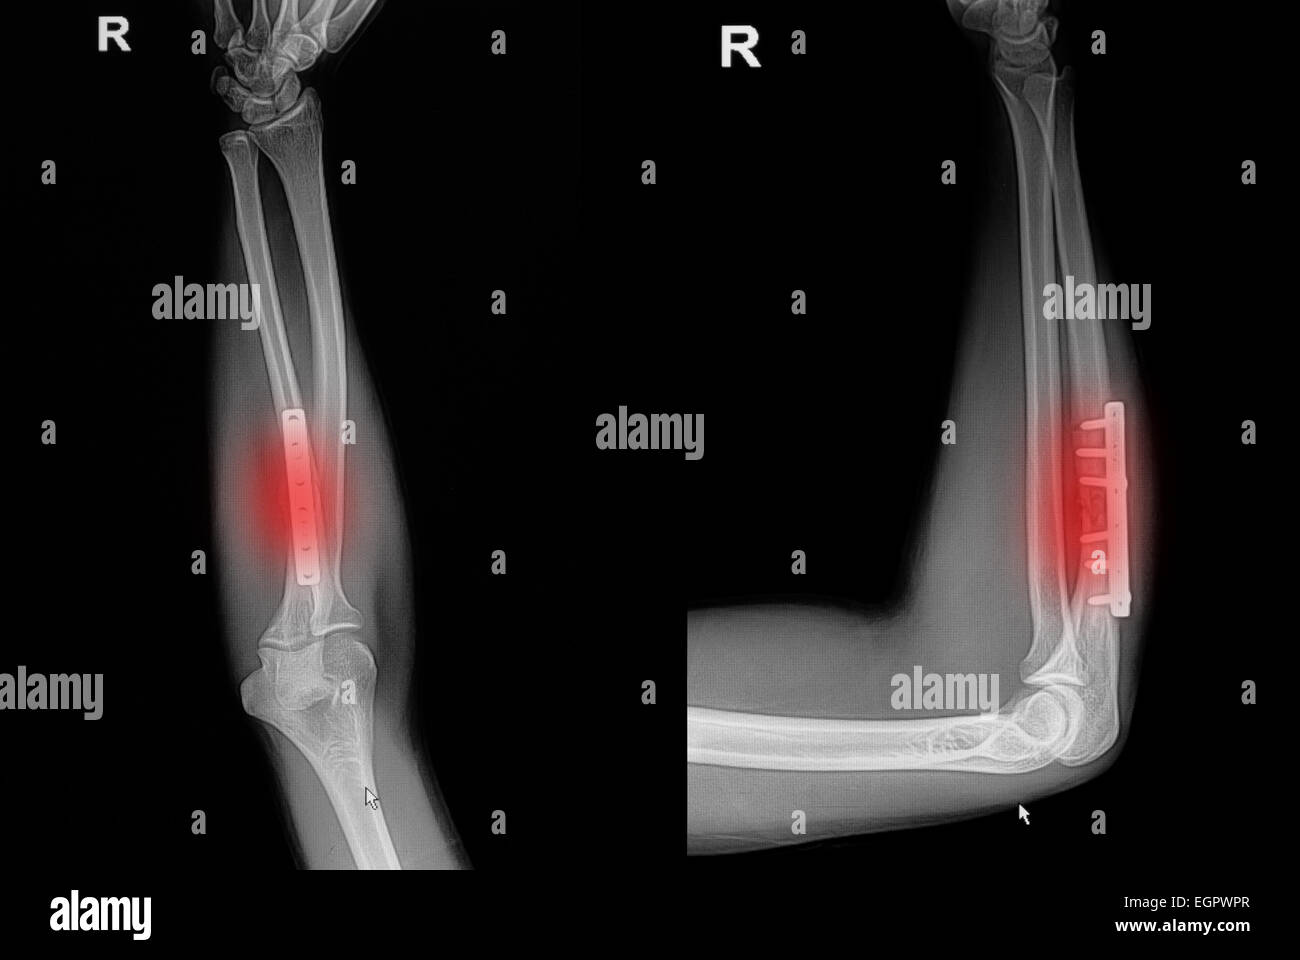

From www.alamy.com

Pinned fractured radius arm bone, Xray Stock Image C055/1142 Radius Bone X Ray Radii) is one of the two long bones present in the forearm, located laterally in the supinated anatomical position. Use the many eponyms with caution. Learn about the causes, symptoms, diagnosis and treatment of distal radius fractures, the most common type of forearm fracture. Typical fracture patterns arise in the forearm bones. What is a fracture of the distal radius?. Radius Bone X Ray.